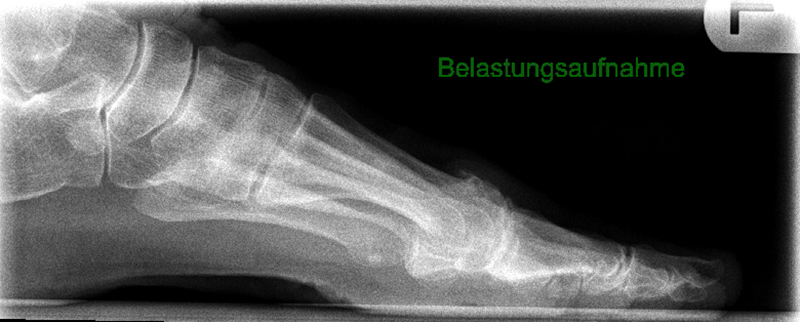

• Röntgenaufnahmen des Vorfußes (unter Belastung) im dorsoplantaren und seitlichen Strahlengang (Abb. 1a+b)

• Beurteilung des Erkankungsstadiums anhand der typischen Arthrosekriterien (Einteilung nach Regnauld). Beurteilung des Intermetatarsal-Winkels (IMA), des Hallux valgus-Winkels (HVA), da nur geringe Korrekturmöglichkeit durch die Osteotomieebene, darüber hinaus evtl. zusätzliche basisnahe MT-I-Korrektur notwendig

• Beurteilung der Grundgliedlänge, insbesondere nach Voroperationen, hinsichtlich möglicher Überlänge des Implantat-Stems.